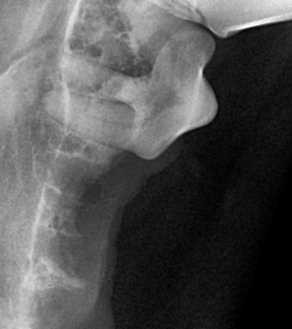

치주염은 반려동물의 잇몸과 치아 주변 조직이 염증으로 손상되는 질환입니다.

입 속 세균이 치석으로 굳어지면서 염증을 일으키고, 시간이 지날수록

특히 강아지와 고양이 모두 3세 이상 반려동물의 80% 이상이 치주염을 겪고 있다는 보고가 있을 만큼 매우 흔하지만,

눈에 띄지 않게 진행되어 보호자가 늦게 알아차리기 쉬운 질환입니다.

치주염은 진행 정도에 따라 1~4기로 분류되며, 기수에 따라 관리 방법과 치료 방향이 달라집니다.

진행될수록 통증 뿐만 아니라 전신 건강에도 영향을 줄 수 있으므로, 조기 발견과 관리가 가장 중요합니다.